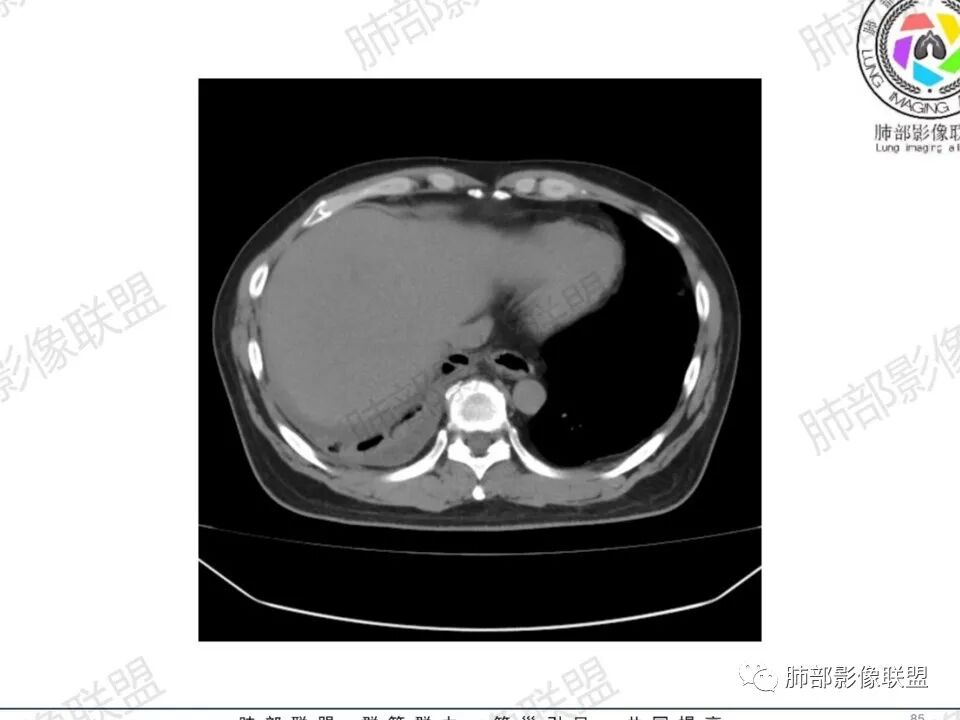

双肺多发结节,胸膜下为主,部分可见空洞。左肺上叶尖后段结节较大,分叶毛刺,周围可见长条索及小斑片影,内空洞比较光滑,内侧壁可见支气管通过。右肺下叶后基底段不张实变,后侧积液,右侧水平裂积液,右侧膈胸膜纵膈胸膜增厚积液,右侧侧胸膜肥厚,考虑1:一元金葡。2二元:金葡,左肺上叶结核。

男,45岁,左手指红肿疼痛两天,右侧胸壁疼痛伴发热12小时入院。患者急性起病,胸部CT示双肺多发结节,部分伴空洞,空洞壁较光滑,右侧胸腔积液,考虑感染性病变,金葡菌加SPE可能

感觉还是金葡入血形成SPE可能性较大,胸水+楔形影+胸膜结节

中年男性,左手中指及胸壁疼痛伴发热来诊,影像见双肺多发结节,胸膜下分布为主,部分结节可见空洞,边缘模糊。左肺上叶尖后段结节较大。右肺下叶后基底段不张实变,右侧叶间裂及右侧胸腔积液,右侧侧胸膜肥厚。考虑金葡菌感染,血播SPE。

两肺多发结节空洞,随机分布,右肺下叶部分病灶实变并胸膜腔少量积液,有皮肤破溃,手指疼痛,发热,考虑感染性变,金葡可能性大。

有胸腔积液更提示血道来源